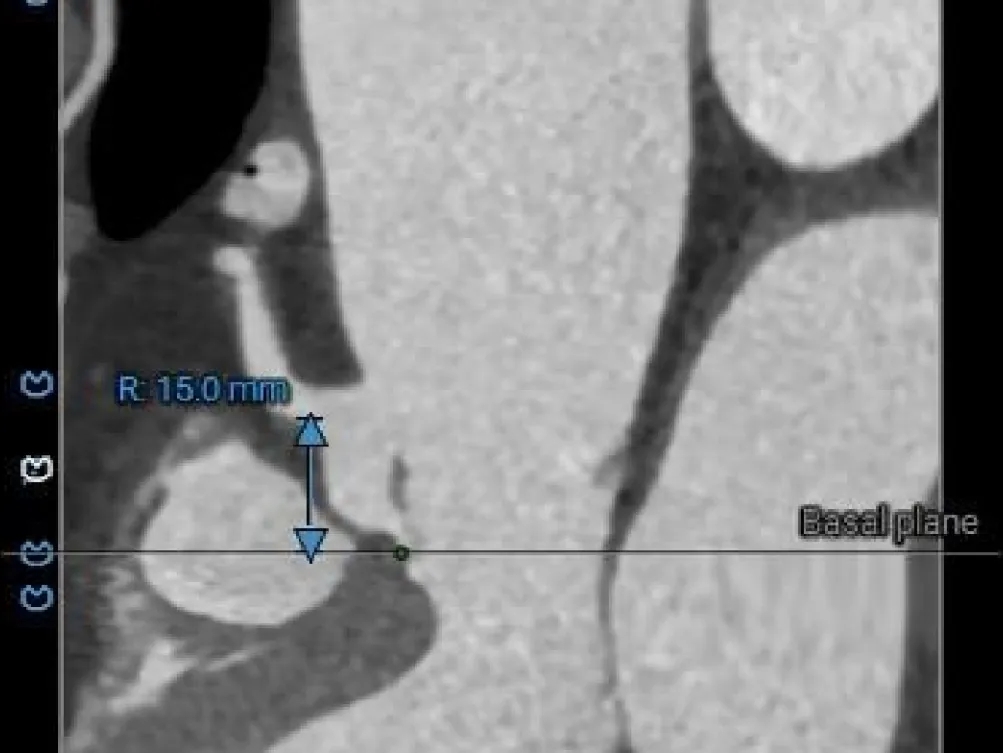

冠脉风险评估

LCA Height

RCA Height

LCA & Leaflet

RCA & Leaflet